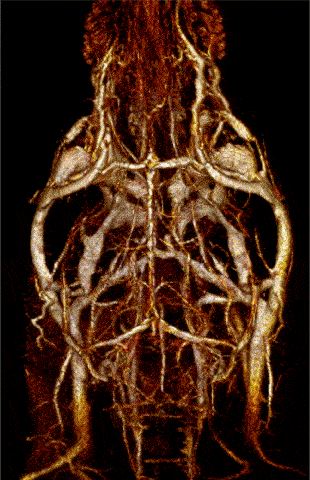

MR angiography with high T1 relaxivity liposomal-Gd contrast agents produces reconstructed 3D map of the cerebral vasculature of a mouse brain. Image Credit: Scintica Instrumentation Inc

Dynamic contrast-enhanced (DCE-) MRI shows the change in T1-signal following the remote intravenous injection of a T1 contrast agent via the lateral tail vein, which can be used to quantify vascular perfusion. Image Credit: Scintica Instrumentation Inc